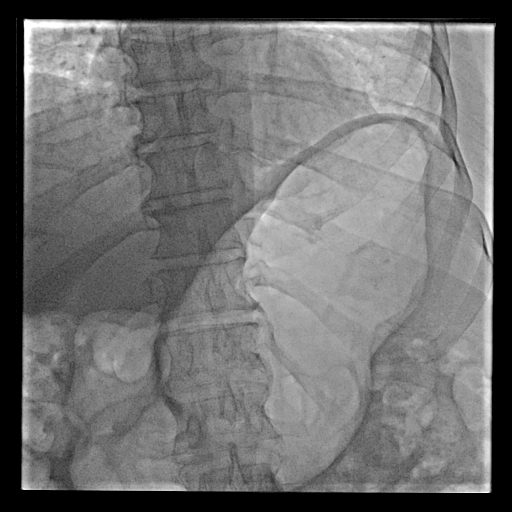

On fluoroscopy, his stomach was dilated significantly; however, there was no vomiting, and he was passing voluminous flatus, so we did not suspect any obstruction in the gut (Figure 1). He had never experienced these kinds of abdominal symptoms prior to this illness. On coronary angiogram, his left anterior descending and left circumflex arteries were almost normal with codominant circulation. His right coronary artery (RCA) was occluded in the mid-segment (Figure 2). He had a brief episode of ventricular tachycardia, which was reverted with direct current cardioversion and a short-duration cardiopulmonary resuscitation. ECG showed that the right ventricle was mildly dilated with thinning, as well as a small aneurysmal bulge in the basal wall. He underwent percutaneous transluminal coronary angioplasty and stenting in the RCA. His subsequent stay in the hospital was uneventful. The next day, an x-ray was performed on his abdomen, which was grossly normal without any features of obstruction.